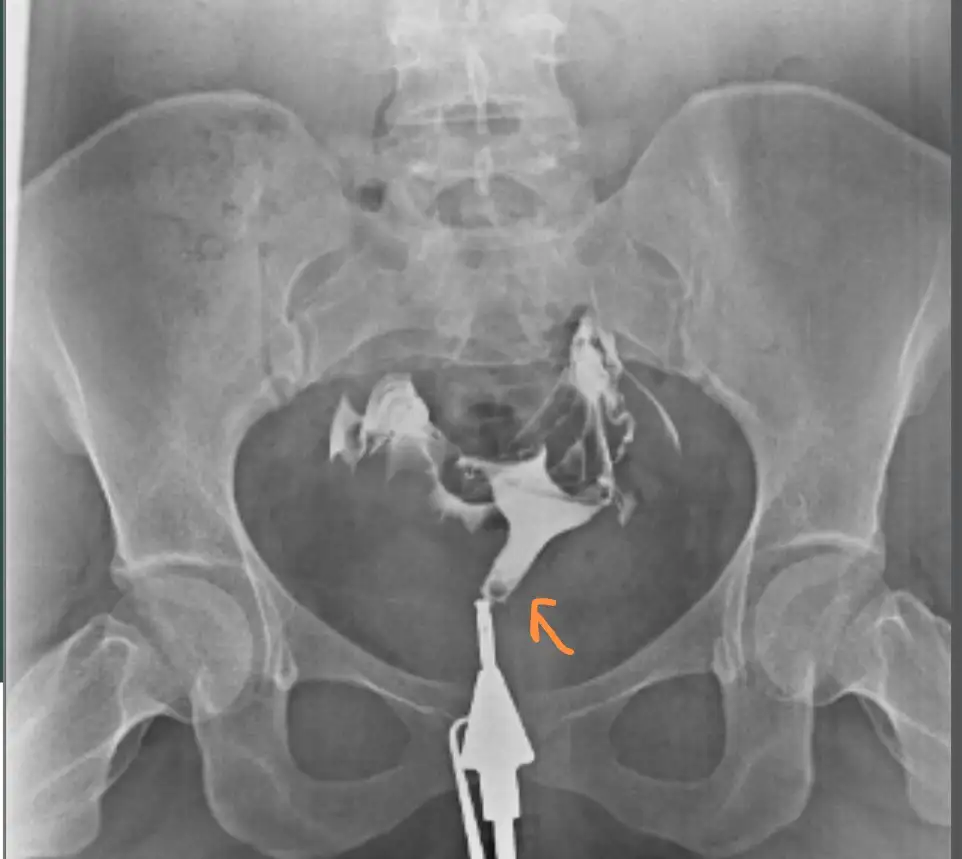

Yumurta değil bence canım. Adet sonrası hemen yumurta olmaz ki. Bu arada canın acıdı mı nasıl çektirdin hsg. Bende Cumartesi gidicem çektirmeye çok korkuyorumKızlar dün hsg çektirdim bu küçük şeyler yumurta olabilir mi

Her iki tubalarda açık yazıyorCanım hsgden sonra rapor kağıdı veriyorlar ya orda ne yazıyor

Evet canım çektirdim. Bende oraya gittim, bir sorun yapmadım. Regle sancısı gibi ağrı oluyor o an geçiyor sonraÇektirdinz mi bende echomar gideceğim